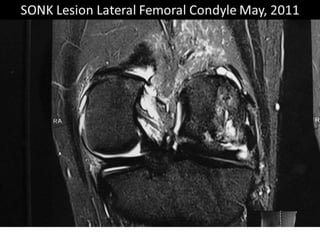

The document presents a detailed case study of a patient with transient osteoporosis of the hip (TOH) and spontaneous osteonecrosis of the knee (SONK) treated at Choithram Hospital & Research Centre in India. Over 20 years, the patient experienced multiple episodes of TOH and SONK with no history of trauma or co-morbidities, resulting in resolutions and recurrences of conditions. The information is intended for orthopedic surgery students and highlights personal experiences and case collections, with a disclaimer regarding content usage and potential controversies.